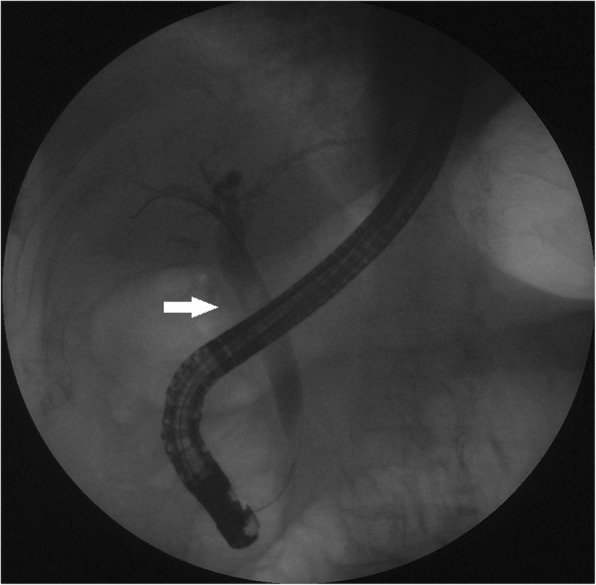

A 75-year-old woman was admitted to the hospital with abdominal pain, nausea and vomiting for 3 days. She did not drink alcohol, and there was no clinical or biochemical evidence of primary liver disease or coagulopathy. Physical examination revealed mild tenderness in the right upper abdominal quadrant. Laboratory tests revealed that the percentage of neutrophils (N%) was 80.3% (50–70%), alanine aminotransferase (ALT) was 192 U/L (< 64 U/L), aspartate aminotransferase (AST) was 66 U/L (< 64 U/L), γ-glutamyl transpeptidase (γ-GT) was 197 U/L (< 47 U/L), and all other laboratory parameters were normal (e.g., haemoglobin and platelet counts, prothrombin time, and renal function). An abdominal computerized tomography (CT) scan demonstrated dilatation of the extrahepatic bile duct with a stone at the lower CBD and sludge in the gallbladder. (Fig. 1) Bile duct cholangiopancreatography revealed a dilated CBD (10 mm in diameter) with a round filling defect (8 mm in diameter) (Fig. 2). Balloon dilation (10 mm in diameter) of terminal CBD after a 5-mm long sphincterotomy for extraction of the stone was uneventful. Unfortunately, she presented with cholangitis and a significant increase in the percentage of neutrophils (94%) and cholestatic parameters (total bilirubin 111.1 μmol/L (2–18 μmol/L), direct bilirubin 81.3 μmol/L (< 7 μmol/L), ALT 465 U/L, AST 538 U/L, and γ-GT 634 U/L) after 3 days.